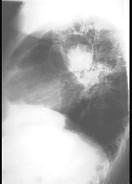

问题 男,48岁,发热,咳嗽,咳痰,咯血,PPD(-),请结合图,最可能的诊断是 ( )

选项 A.肺癌 B.肺曲菌病 C.肺结核 D.肺炎 E.肺脓肿

答案 B